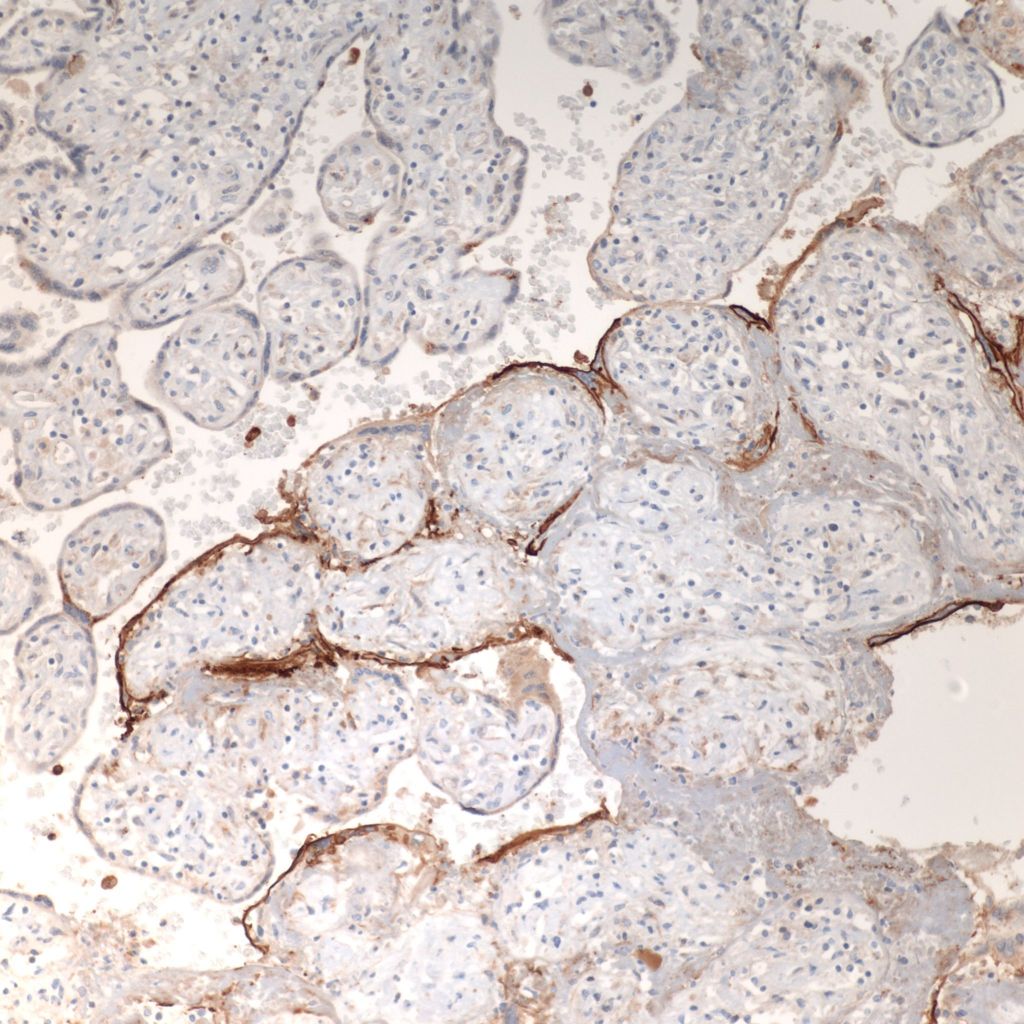

CD68 or alkaline phosphatase: to confirm that the intervillous cells are monocytes, but is not required for meeting the diagnostic criteria

C4d: to show evidence of complement fixation on the microvillous surface of the syncytiotrophoblast. While further study is needed, the subclassification of intervillous monocyte accumulations into those with and without complement fixation and the subclassification of villitis of unknown aetiology with intervillous monocytes into those with and without complement fixation may prove to be a useful distinction.

C4d: One study of CHIV compared 3 histologic groups of placentas demonstrating intervillous histiocytes: Few intervillous monocytes, massive intervillous monocytes, and intervillous monocytes associated with villitis of unknown aetiology18. Each group was further divided into subcategories based on the extent of c4d immunostaining of the microvillous surface of the syncytiotrophoblast. The outcome variables were fetal death or growth restriction. In the analysis, without a formal ROC study, it appeared that staining less than 25% of the villous surface was a natural cut off point from greater than 25%. As can be seen in the Table 1 of the raw data, that with rare exceptions, all the cases with less than 25% of c4d trophoblast staining, and often without any staining, were either associated with few intervillous monocytes, or with villitis. Fetal death or growth restriction was almost always associated with more than 25% of the villous surface stained with c4d. The lack of statistical significance in the comparisons is likely due to small sample size.

1. Direct evidence of Immune injury in intervillositis: The accumulation of monocytes in the intervillous space is the dominate evidence of an immune origin of intervillositis. The accumulation is likely due to both a chemotactic response and increase in either a cell adhesion molecular on the monocyte surfaces or possibly a secondary ligand that is linking monocyte surface molecules. One piece of evidence of an immunologic injury is the staining of the microvillous surface of syncytiotrophoblast by c4d, a stable complement product used routinely in pathology laboratories in identify antibody-mediated rejection in biopsies of transplanted organs. T-cells have been identified as a minority population in intervillostitis, but a regulatory role cannot be excluded. There is evidence in one study of in vitro T-cell activation.